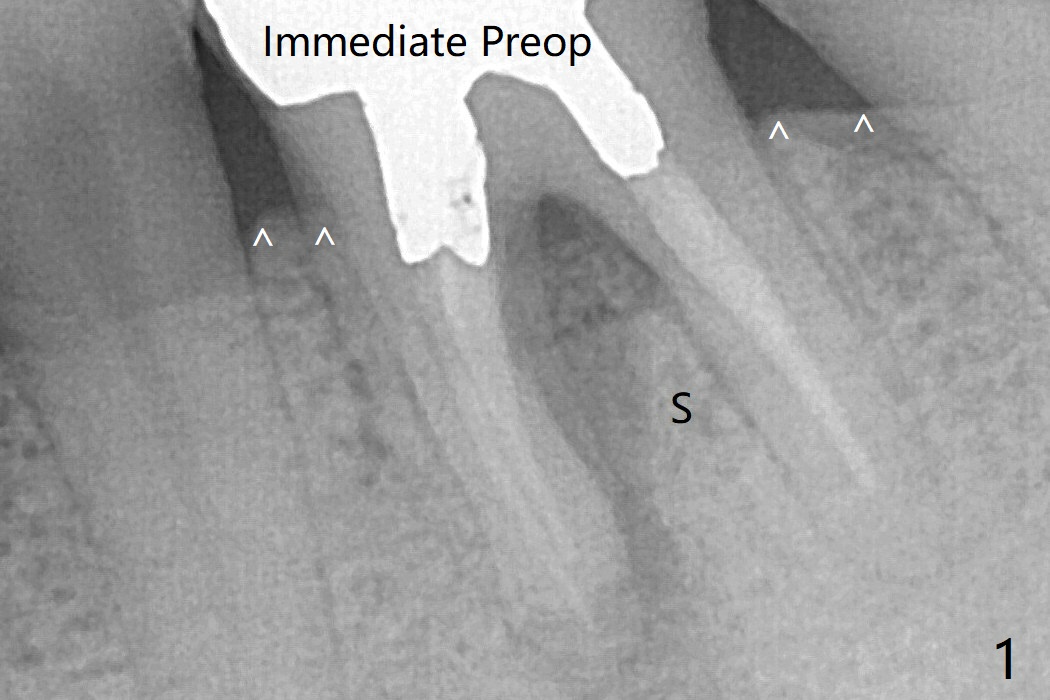

In spite of no apparent loss of bone graft (Fig.4,10), the graft seems to shrink in height 3.5 months postop (Fig.11), while the crest decreases (compare Fig.1 and 11).53岁男左下6因近中根周围阴影(图一)拔除植骨(图四)。术后16天骨粉好像没有失去(图十),但是术后3.5月骨粉仿佛收缩(图十一),牙槽嵴接近牙槽窝处下降(比较所有图)。